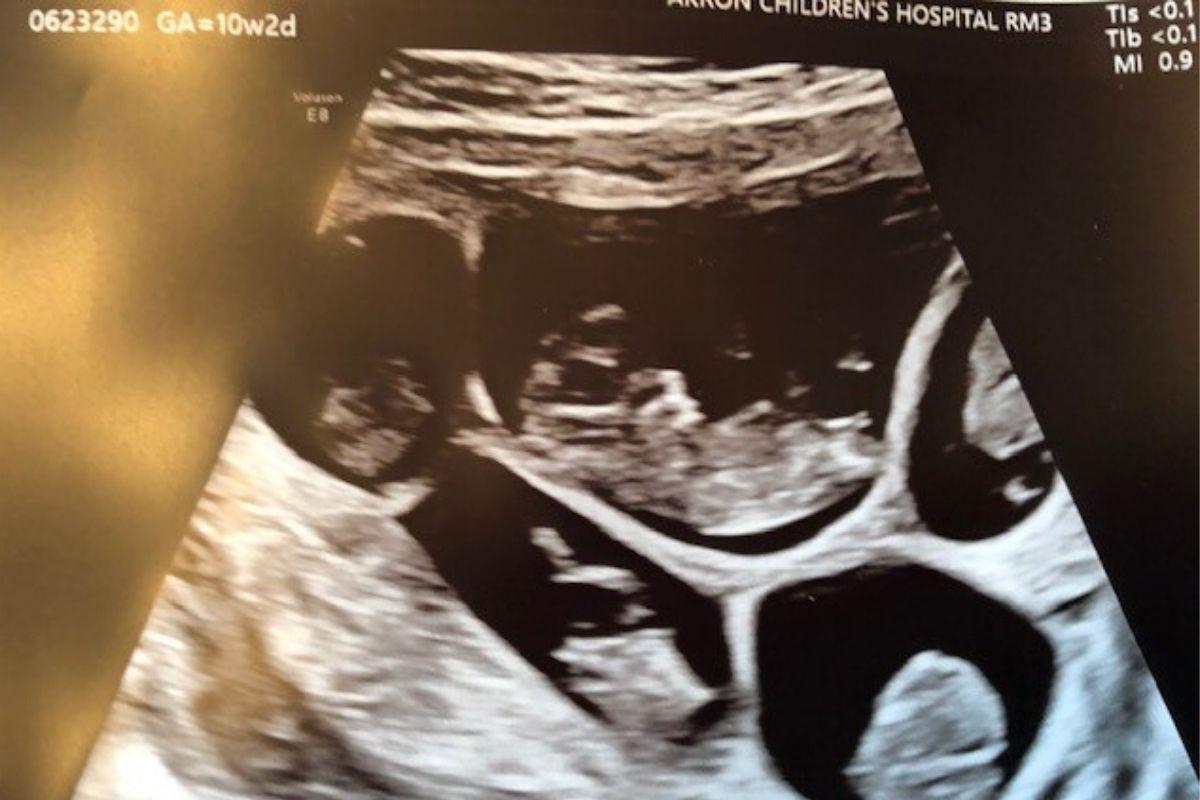

No primeiro ultrassom, os pais puderam identificar os bebês como A e B, mas depois de uma inspeção mais detalhada, os C, D e E também foram descobertos, ou seja, os pais estavam esperando por quíntuplos! “Ela continuou olhando, medindo, contando e recontando. Finalmente, depois que acabou, ela teve que puxar uma cadeira porque estava muito chocada e pensou: ‘Você está grávida de cinco bebês’. Eu estava tipo, ‘Como isso é possível? O quê?”, contou à News 5 Cleveland.